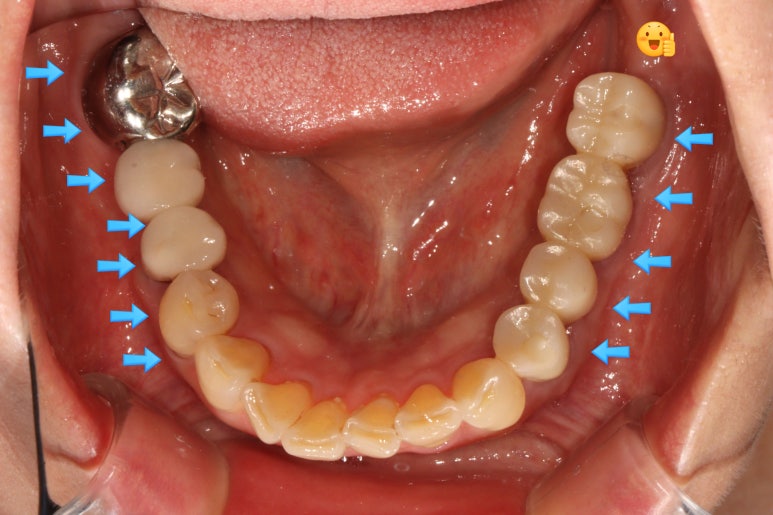

치료 완료 후 단단한 잇몸과 볼점막의 경계인 MGJ를 화살표로 표시해 보았는데요,

처음 오셨을 때의 사진을 참고해보시면 이해가 편하실거에요.

아무 치료도 하지 않고 브릿지로 치료가 되어있던 부분은 단단한 잇몸이 하나도 없이 대부분 볼점막의 경계를 갖고 있습니다만,

제가 유리치은이식술을 하면서 지르코니아 임플란트 크라운을 제작해드렸던 부분은

이식해놓은 단단한 잇몸이 아주 깔끔하게 자리잡으며 최적의 컨디션을 보여주고 있습니다.